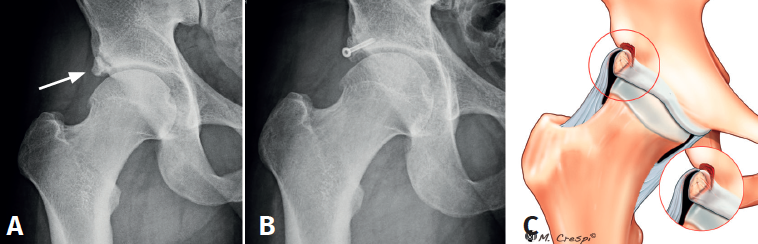

(A3) Fragmentos grandes con una línea vertical en el borde acetabular superior-lateral compatible con fracturas por estrés consolidadas o no consolidadas

- Características y morfología radiográfica: tamaño grande y línea de fractura perpendicular o vertical en relación con el techo acetabular (Figura 3).

- Localización y lesiones asociadas: generalmente, medio lateral o ligeramente posterior en relación con el acetábulo y también con morfologías de CFA asociadas.

- Tratamiento: dependiendo de la cobertura que quede tras la extirpación, se decidirá si enuclear el fragmento o fijarlo. La planificación preoperatoria es por tanto crucial para garantizar que la escisión de la fractura/fragmento no dé como resultado una cobertura insuficiente o una inestabilidad iatrogénica. La medición del ángulo centro borde lateral y anterior al nivel de la extirpación planificada puede dar una indicación de una cobertura insuficiente resultante si el fragmento contribuye a la estabilidad de la cadera. En estos casos, debe considerarse la fijación quirúrgica mediante fijación con tornillo canulado asistida por artroscopia a través de la unión fibrocartilaginosa(4). En casos de fragmentos grandes que contribuyan simultáneamente al pinzamiento y la estabilidad, se puede realizar resección parcial y fijación del remanente. La utilización de una sutura sobre el tornillo de fijación ayudará a realizar la fijación labral sin tener que usar un arpón o anclaje(4)(Figura 4).